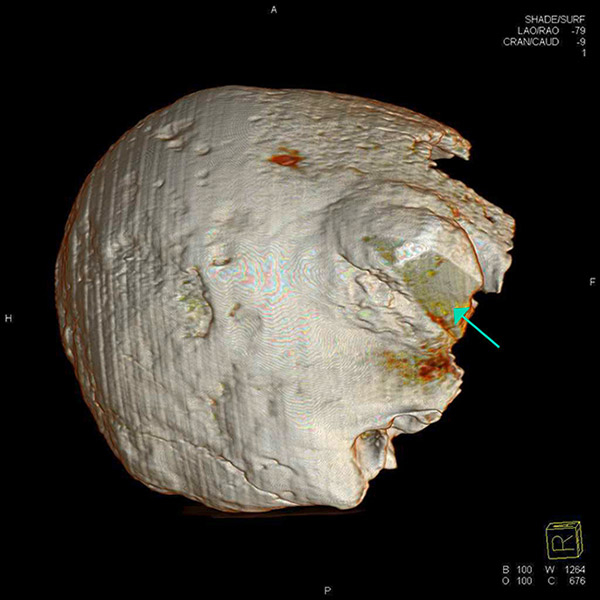

Figure 6

Computed tomography three-dimensional reconstruction of the skull. Wedge-shaped area in the centre of the lesion filled with material of lower X-ray density than the adjacent bone (green arrow).

The remains are well preserved. Morphological examination of skull and pelvis clearly classify the individual as female. The age at death was between 30 and 50 years. There is an intensely calcified bone proliferation at the right side of the os frontalis (fig. 2). Plain X-ray and CT imaging show a large (5.3 x 3 x 8.7 cm) sclerotic lesion in the area of the right temple with a partly bulging appearance (fig. 4). Figure 5 shows representative slices of the admission CT. A differentiation between tabula interna, diploë and tabula externa is not possible in major parts of the lesion. The inner boundary of the lesion shows multiple smooth-edged irregularities. There is a diffuse thickening of the right skull vault (right 7 mm, left 4 mm). The left skull vault presents a mix of sclerotic areas and areas with normal appearance with a clear differentiation between tabula interna, diploë and tabula externa. CT imaging and plain X-ray show a wedge-shaped area in the centre of the lesion that is filled with material of lower X-ray density than the adjacent bone (figs 5 and 6). Histology shows mature organised lamellar bone tissue with ordered formation of trabeculae (figs 7–9). No pathological alterations were found in the postcranial bones.